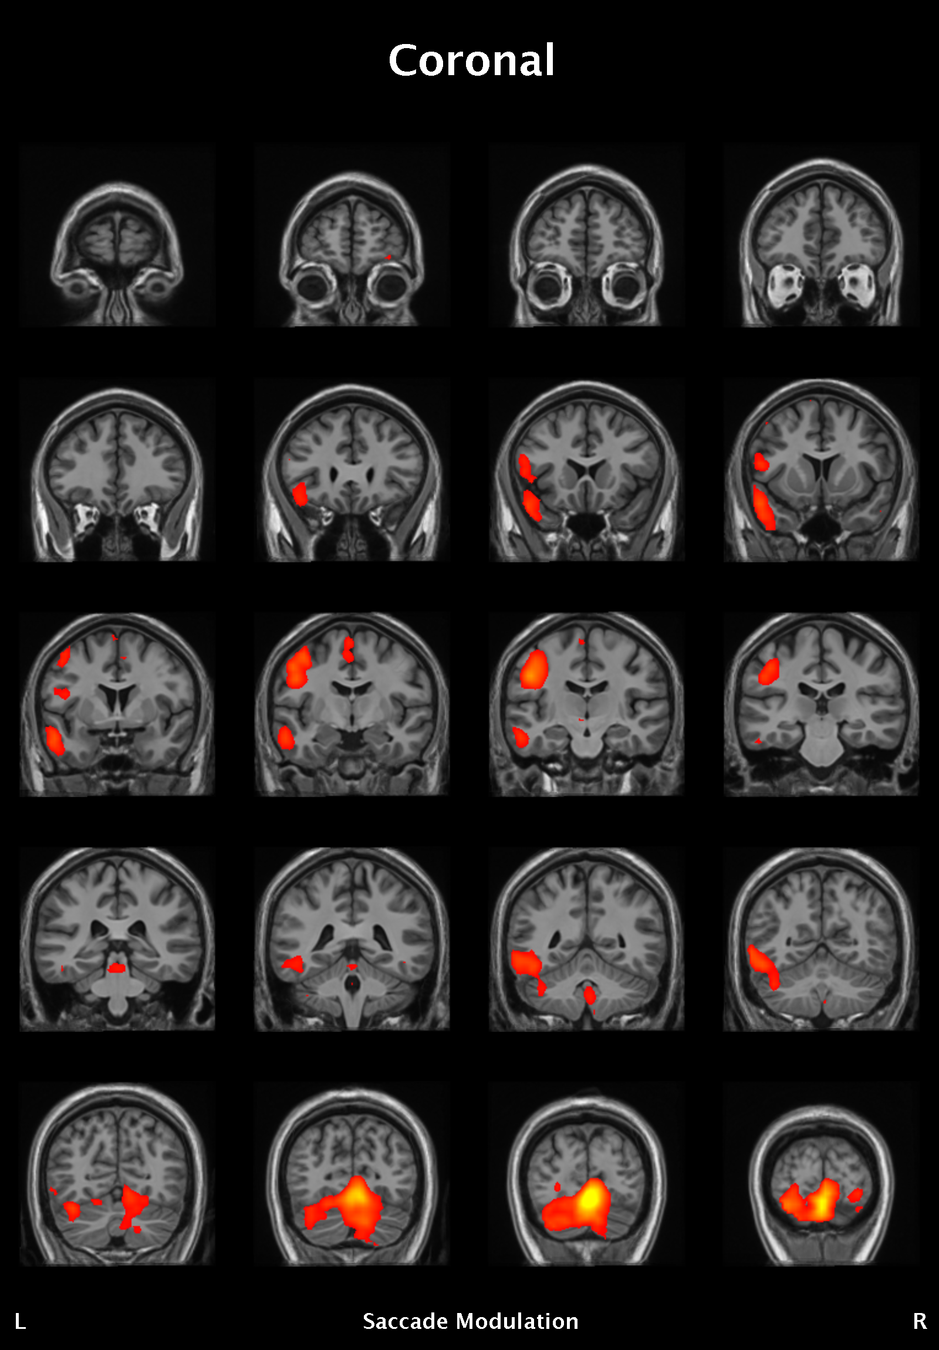

Results

Significant ROIs

Voxels Peak - x Peak - y Peak - z Anatomical location

1923 -1.5 79.5 -9 R/L Lingual Gyrus

495 52.5 -10.5 -18.0 L. Mid. Temporal Gyrus

395 46.5 16.5 33.0 L. Precentral Gyrus

135 1.5 38.5 -12.0 L. Ant. Cerebellum

56 7.5 19.5 -3.0 L. Thalamus

55 -22.5 -94.5 -9.0 R. Inf. Occipital Gyrus

55 52.5 -7.5 15.0 L. Inf. Frontal Gyrus

54 4.5 7.5 60.0 L. Medial Frontal Gyrus

29 -46.5 -7.5 -24.0 R. Temporal Pole